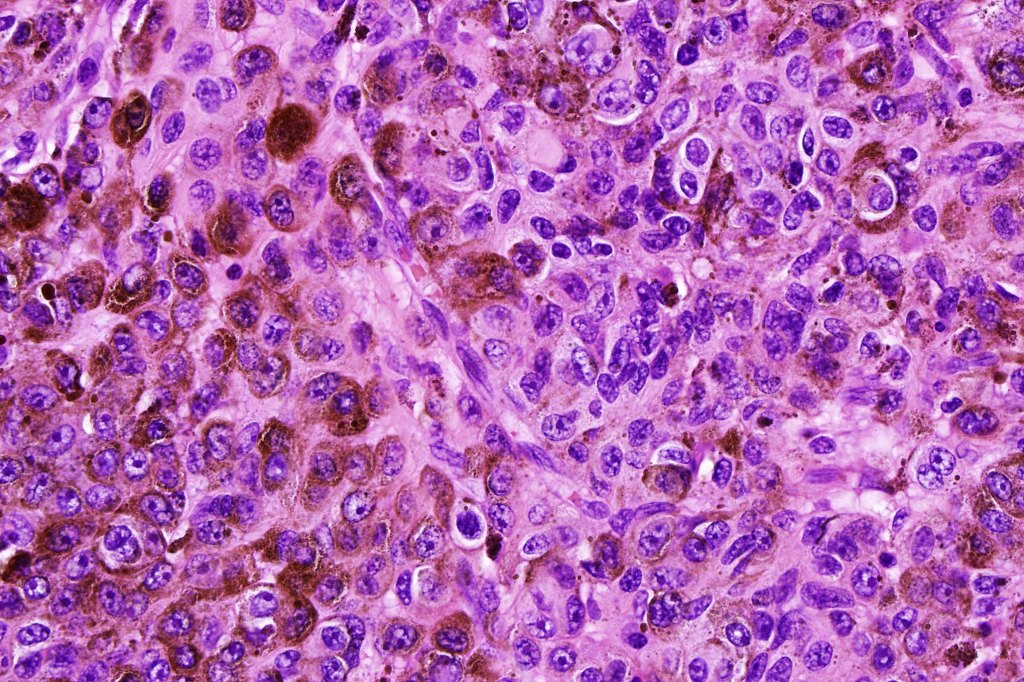

•Typical melanoma, nevoid melanoma, small cell melanoma, pleomorphic/anaplastic melanoma, melanoma with heterologous differentiation & malignant nerve sheath-like melanoma.

This melanoma arose in a small congenital nevus of the scalp. It metastasized widely. Varying features in different fields.